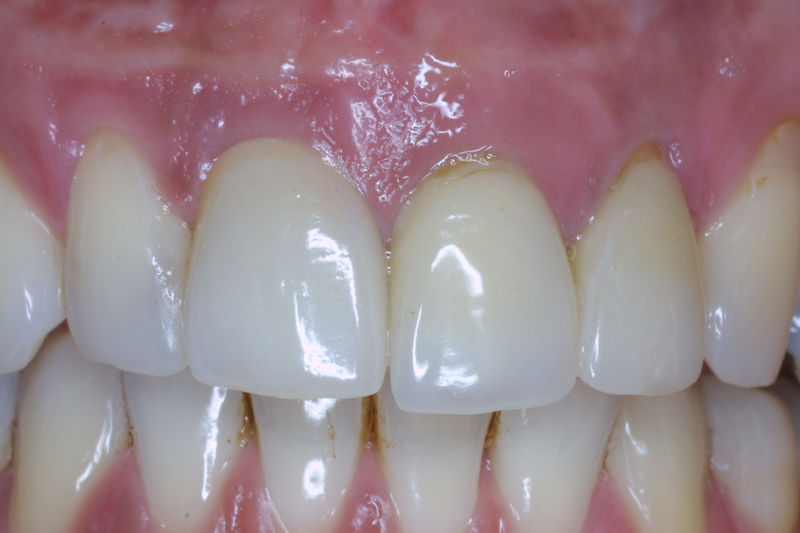

Son restauraciones que cubren toda la cara frontal del diente, generalmente empleadas en el sector anterior y cuya finalidad es primariamente estética.

Restauraciones fabricadas en el laboratorio con materiales estéticos, los cuales cubren de manera total dientes anteriores y posteriores. Se utilizan primariamente para restaurar dientes con caries, fracturas y/o defectos amplios, así como soportes de puentes. Para poder enviar el caso al laboratorio se toman impresiones utilizando materiales de impresión o técnicas modernas digitales.

Amplia gama de tratamientos para mejorar la apariencia de la sonrisa, corrigiendo el color, la forma, el tamaño, la alineación y la posición de los dientes. Los procedimientos más comunes y solicitados incluyen el blanqueamiento dental, las carillas y coronas, así como las resinas.